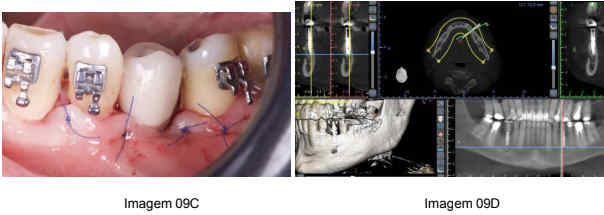

Após o período de cicatrização e osseointegração de aproximadamente 6 meses, o paciente foi reavaliado e, com base nos exames clínicos e radiográficos, constatou-se que o implante estava completamente osseointegrado. A segunda fase do tratamento envolveu a reabertura do local para a remoção dos parafusos de titânio e a instalação da coroa definitiva, proporcionando ao paciente função mastigatória adequada.

(Imagem 09A, 09B e 09C)

Fonte: próprio autor

O acompanhamento pós-operatório foi realizado com o paciente a cada semana, para avaliar a cicatrização e monitorar possíveis complicações. O paciente foi orientado quanto ao uso de medicamentos analgésicos e anti-inflamatórios, além de cuidados com a higiene bucal e dieta. (Imagem 10A e 10B)